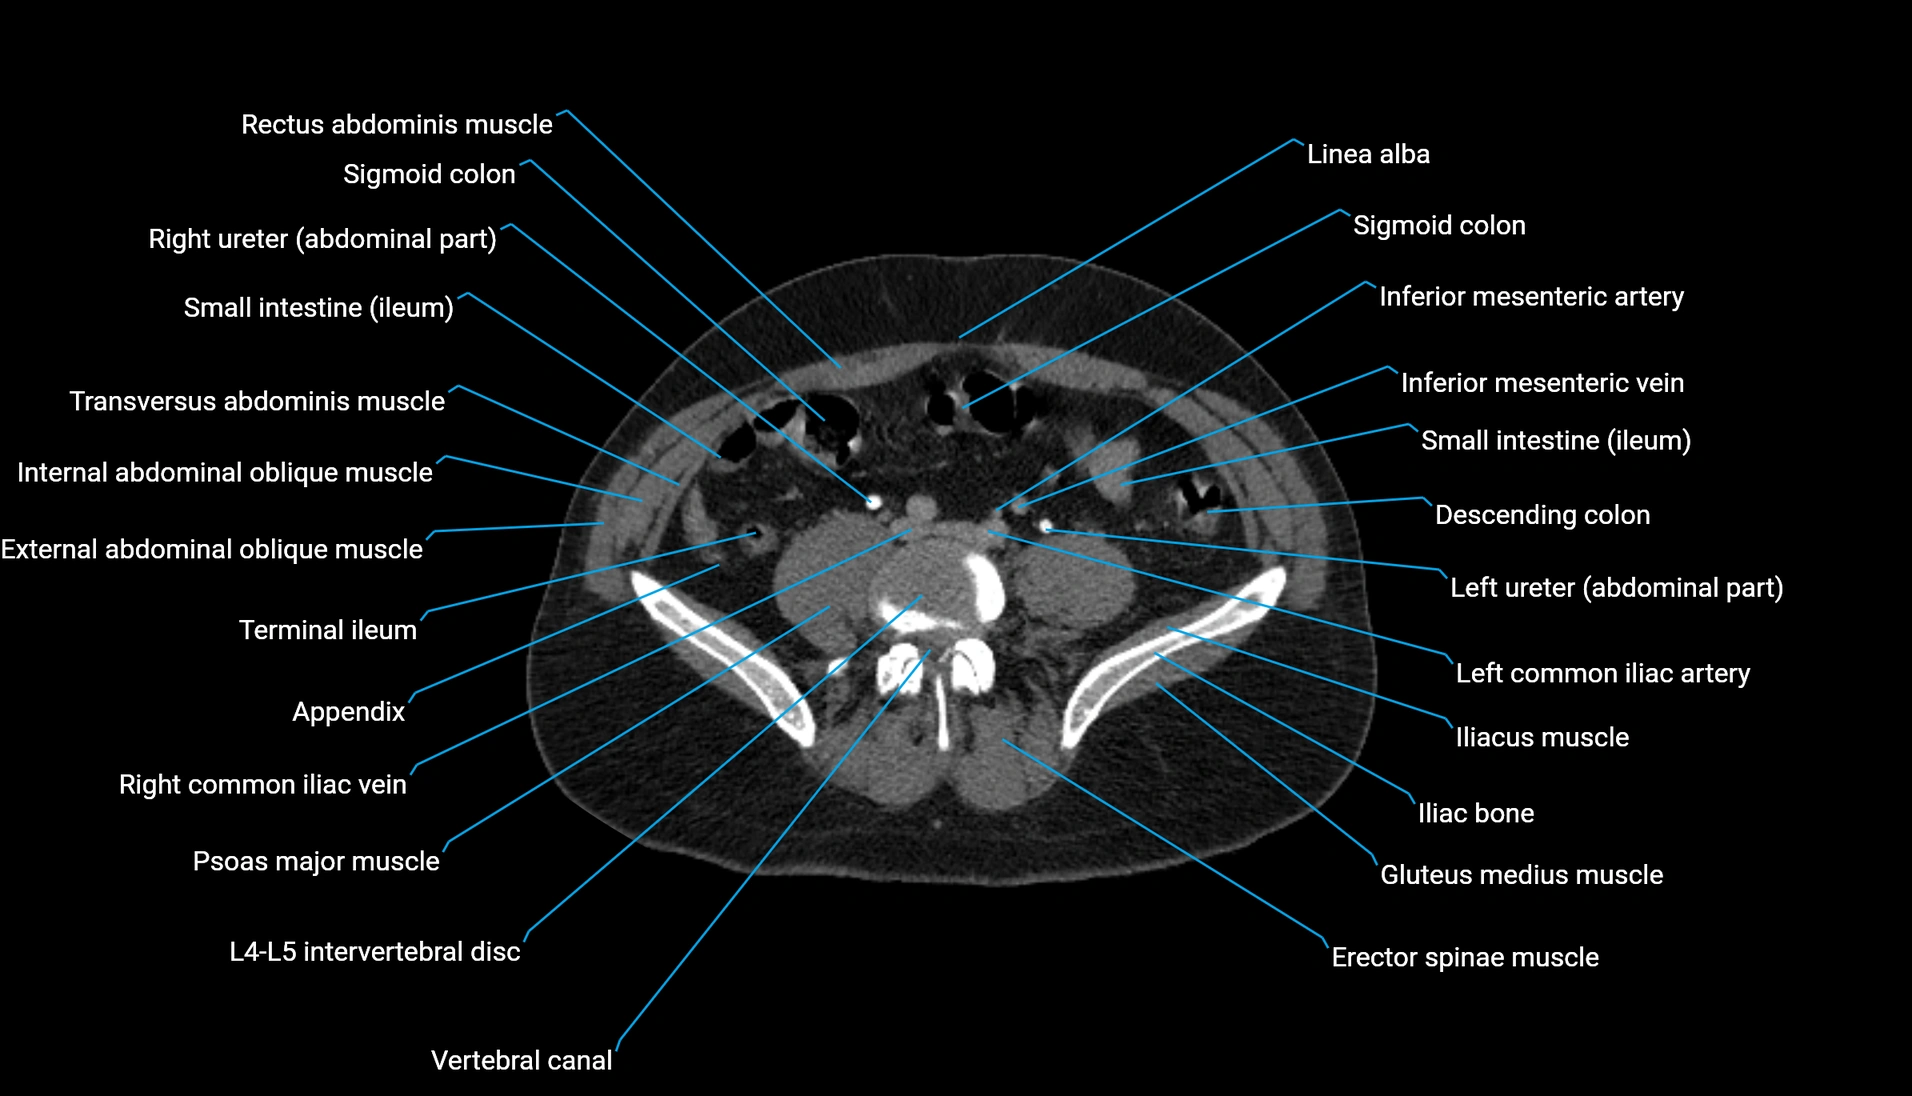

CT image